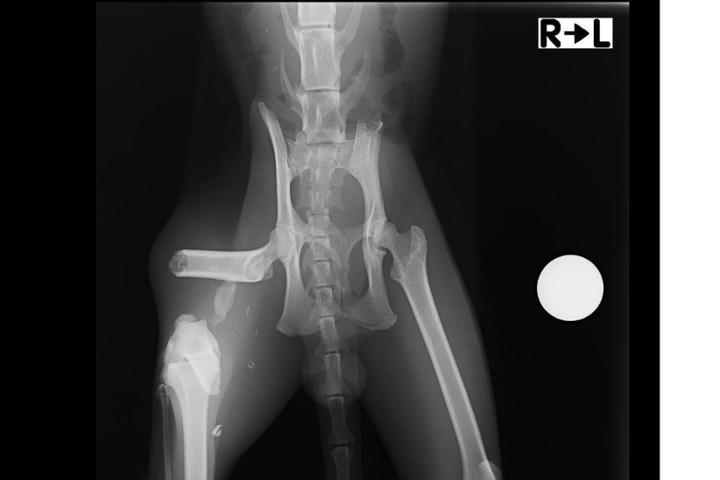

Fijación de fractura de fémur de Axel

Axel es un gatito que vivía en la calle. Nos dieron aviso de que había un gato con mal aspecto y que le pasaba algo en la pata. Estuvimos intentando capturarlo durante varios dias sin éxito, ya que es un gatito desconfiado. Pero al final con paciencia pudimos cogerlo y llevarlo de urgencia a una clínica veterinaria. Allí nos mostraron la gravedad de sus lesiones. Rotura total de fémur, sin otra solución que operación urgente. Pero su analítica era desastrosa, mucha anemia e infección. No sé podía operar hasta que no estuviera más recuperado. Lleva ingresado desde el día 22 de febrero y fue ya operado el pasado jueves 7 de marzo. El presupuesto de la fijación son 685 €, más lo que ascienda su hospitalización. Agradecemos muchísimo quien pueda ayudarnos, Axel nos necesita. ¡Gracias!